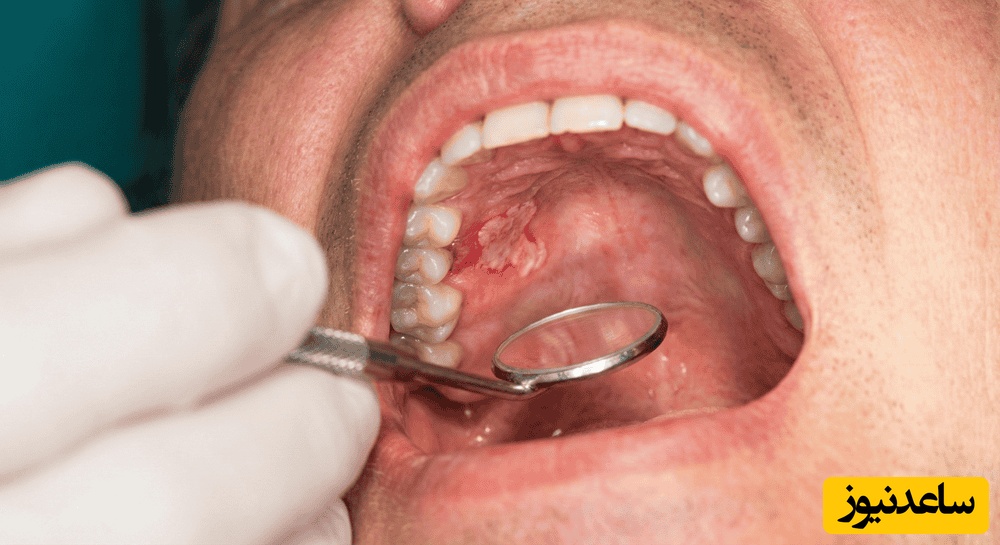

برای غربالگری سرطان دهان نیاز به معاینه ی جسمی کامل و بررسی دقیق سابقه ی پزشکی است. متخصصان باید به صورت چشمی و لمسی نواحی سر، گردن، زخم های دهان و فارینژیال را معاینه کنند.این نوع معاینه شامل معاینه ی انگشتی گره های گردنی، معاینه ی دو انگشتی سقف و کف دهان و زبان، و معاینه با لمس و مشاهده ی مخاط دهان و فارینژیال با منبع نورانی است.استفاده از آینه های دهانی برای این معاینه کاملاً ضروری است.زبان باید کاملاً بیرون کشیده شود تا بتوان به طور کامل مناطق پشتی و انتهایی و پایه ی زبان را مشاهده کرد.

در صورتی که متخصصان بدون بررسی و معاینه کامل جسمی بیمار به تشخیص دیگری غیر از سرطان دهان دست پیدا کنند و به دنبال آن به تجویز دارو بپردازند تشخیص سرطان ممکن است چندین ماه به تاخیر بیفتد .بیمارانی که مشکل آن ها بیش از 2 تا 4 هفته طول کشیده، باید به سرعت و بدون فوت وقت به یک متخصص مناسب ارجاع داده شوند تا تشخیص قطعی برای آنان صورت بگیرد. در صورتی که پزشک با ضایعه ی دهانی مواجه شود، بی درنگ و بدون تاخیر باید بیوپسی انجام شود.

علائم سرطان دهان مثل یک نقشه راه به شما کمک می کند که تا حد زیادی متوجه شوید که در معرض خطر ابتلا به این بیماری هستید یا خیر!برای تشخیص این بیماری دندان پزشک می تواند گردن، سر، صورت و حفره دهان شما را ارزیابی کند و ببیند که توده، برآمدگی یا تغییرات غیر عادی بافت در این نواحی وجود دارد یا خیر. دندانپزشک ضمن بررسی موارد گفته شده می تواند درپی وجود زخم یا تغییر رنگ بافت های دهانی هم باشد.